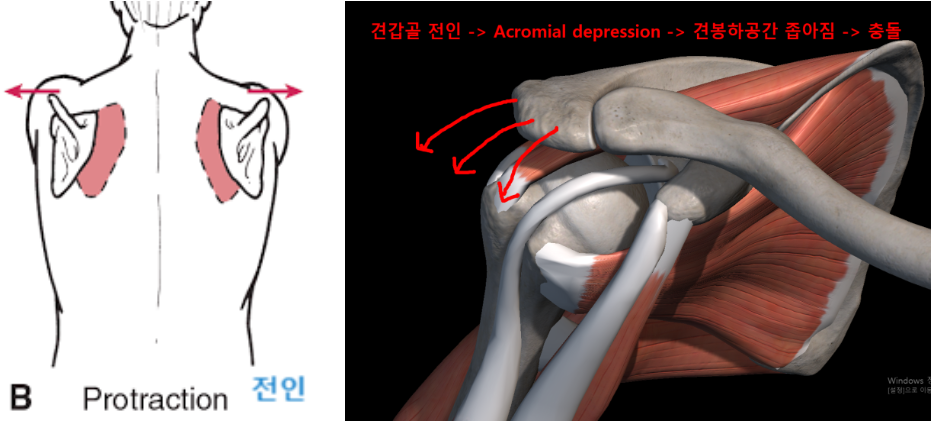

후만과 거북목으로 인해 견갑골이 앞으로 빠지는 전인상태(Scapular protraction)이 되면서 견봉하공간이 좁아지면서 어깨 충돌가능성이 증가할 수 있습니다.

앞서 말했던 원인들에 의해서 겹갑골은 과도한 견갑골의 앞으로 빠진상태인 전인상태(견갑골 벌어짐, Protraction, 후인이 잘 안됨)와 견봉 올림(Acromial elevation)이 어려움에 의해서 충돌이 더욱 쉽게 일아날 수 있습니다.

굽은등, 거북목 -> 견갑골 전인상태 -> 견봉하공간 좁아짐 -> 충돌 증가